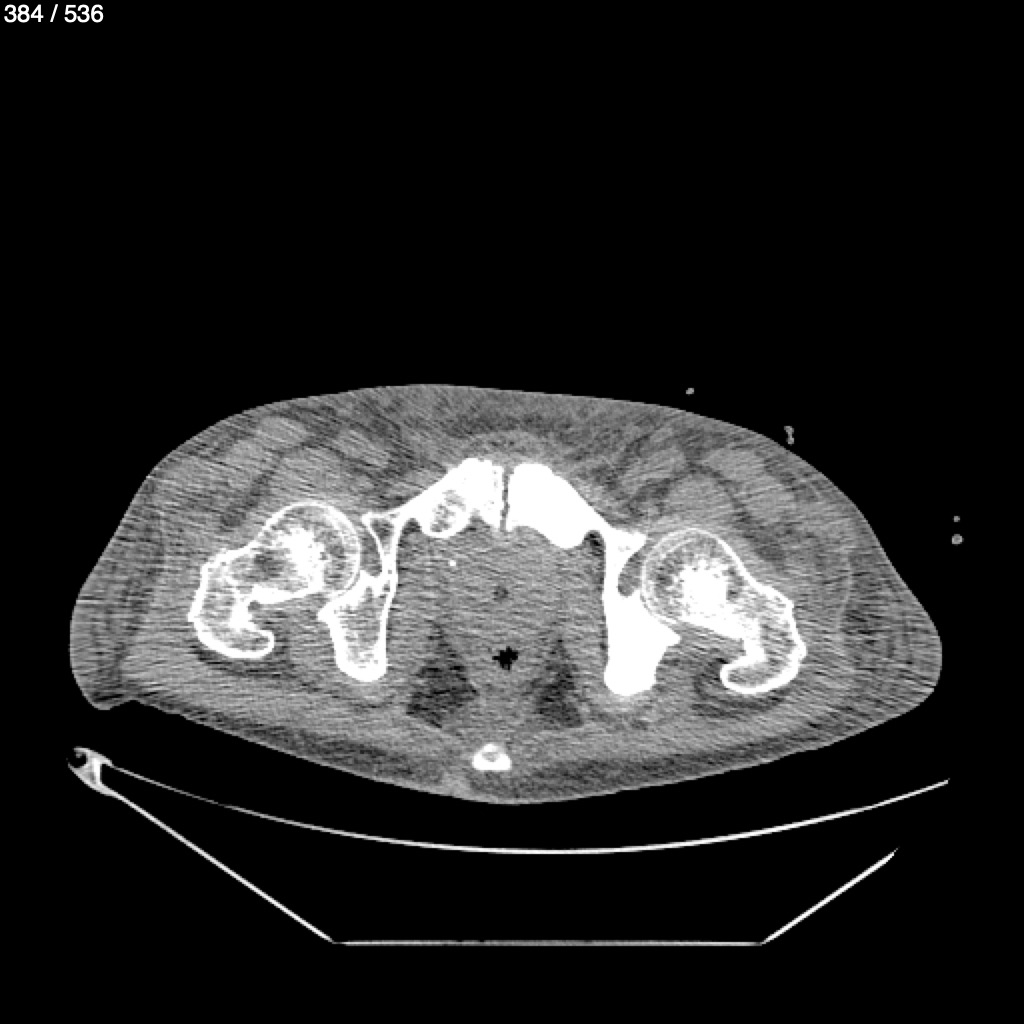

Angel Villalobos Palomeque 73 A - T.C Abdomen Simple